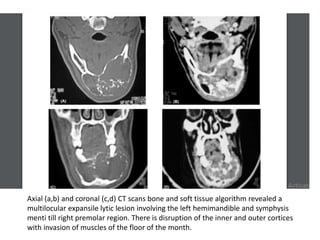

Axial (a,b) and coronal (c,d) CT scans bone and soft tissue algorithm revealed a

multilocular expansile lytic lesion involving the left hemimandible and symphysis

menti till right premolar region. There is disruption of the inner and outer cortices

with invasion of muscles of the floor of the month.